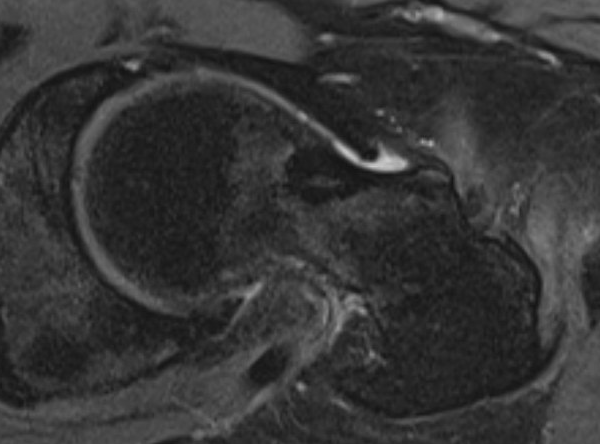

MRI

- Low signal on T1 and T2

- Do not enhance with contrast